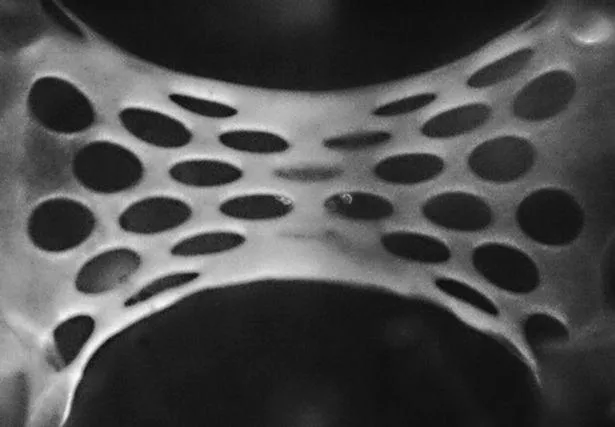

Пластир містить до 50 мільйонів людських стовбурових клітин, які перетворюються на здоровий серцевий м’яз. Розробка містить речовини, які здатні відновлювати та оновлювати клітини серця.

За словами дослідників, пластирі підживлювалися кровоносними судинами, які ростуть від серця реципієнта.